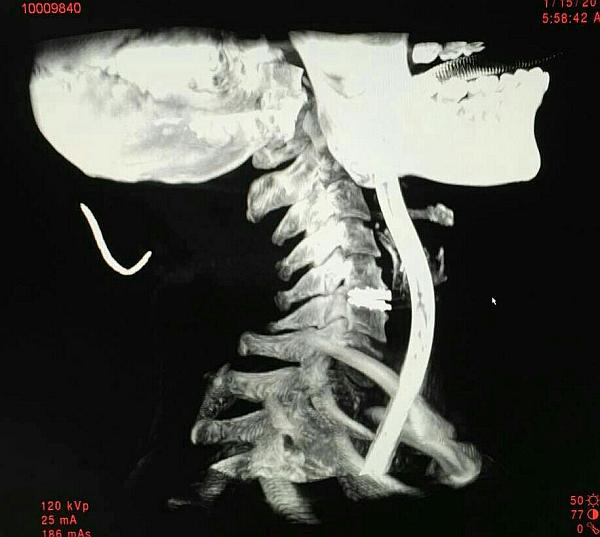

术前O-ARM定位颈5-6椎间盘节段

术中O-ARM确定人工椎间盘位置好